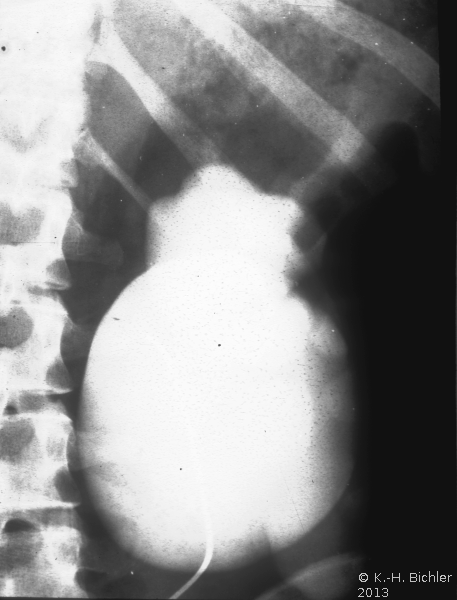

• Abbildung 17: Ureterabgangsstenose mit ausgedehnter Hydronephrose links

2. Spätaufnahme (AUR): Erheblich dilatiertes Nierenbecken links